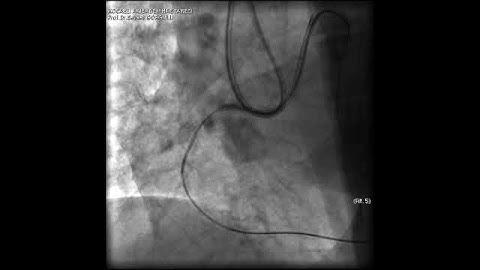

PCI for CTO part -3 retrograde